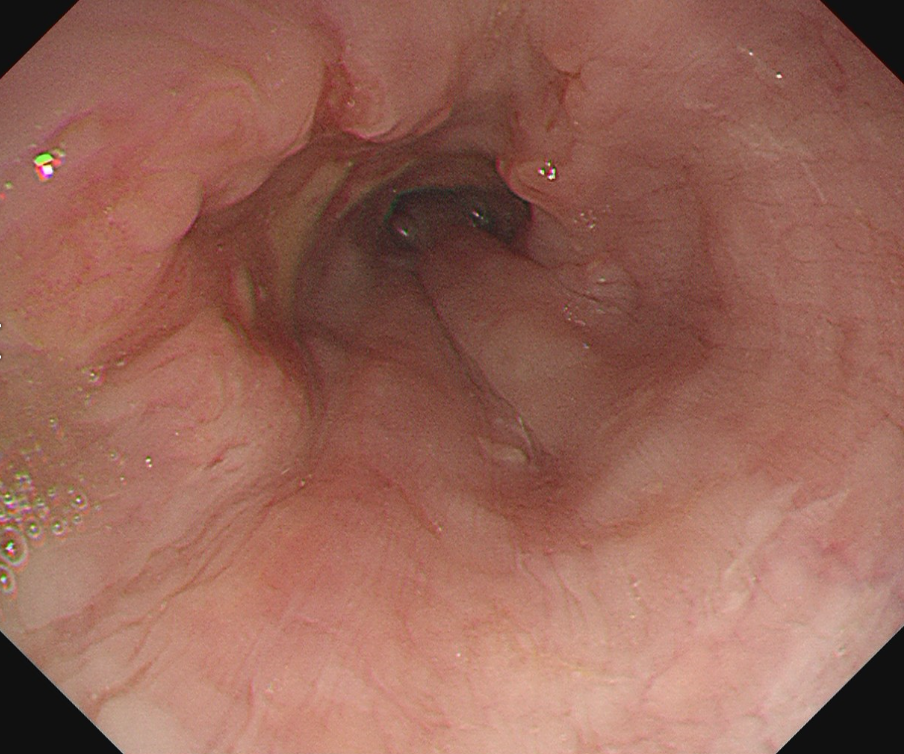

食道がんの検査は、がんかどうかを確定するための検査と確定された後に行う進行度を判断するための検査があります。まず確定するための検査としては、内視鏡(胃カメラ)で直接病変を観察する内視鏡検査が行われます。内視鏡で異常がみられる場合は組織を採取し、顕微鏡で観察する生検を行い診断が確定されます。

内視鏡(胃カメラ)画像